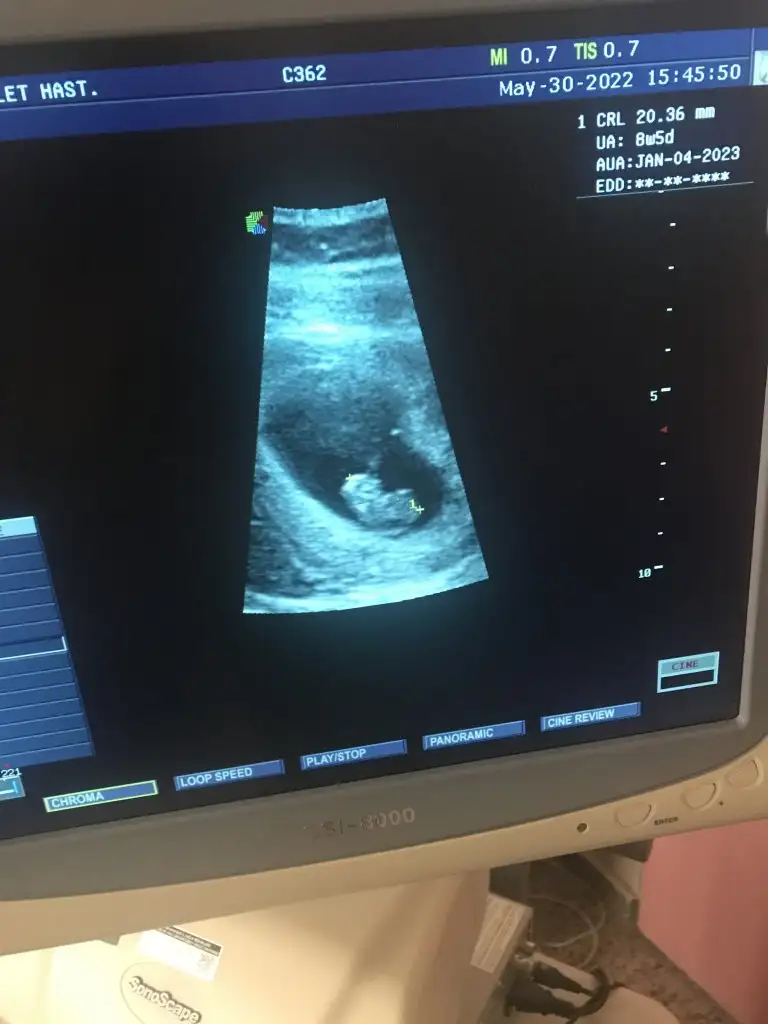

Pasha22 Pasha22 merhaba canim benimkinide yorumlarmisiniz 8+5 karindan

Eklentiler

• 3005436F-1E05-4F19-898D-A7A5DF183F28.webp

3005436F-1E05-4F19-898D-A7A5DF183F28.webp

28 KB · Görüntüleme: 85